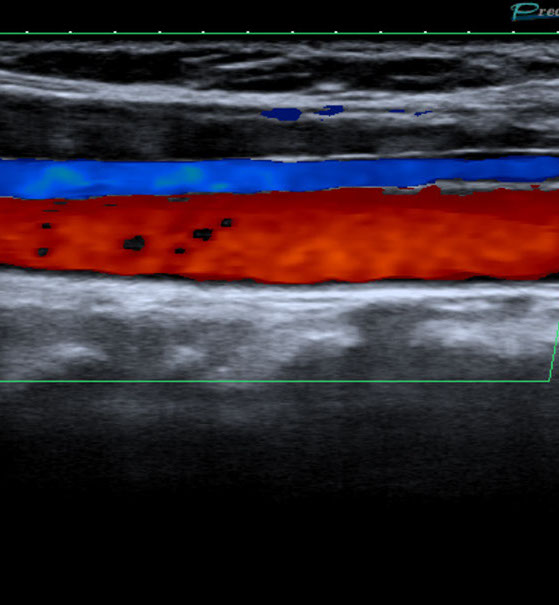

Gefäßultraschall /

Farbdopplersonographie

Die Farbdopplersonographie ist eine zuverlässige Methode zur Beurteilung von Arterien und Venen. Die Farbdopplersonographie kann einerseits Veränderungen der Gefäßwände (z.B. arteriosklerotische Plaques) und dadurch resultierende Engstellen (Stenosen) nachweisen, andererseits durch Blutflussgeschwindigkeitsmessungen den Schweregrad der Stenosen beurteilen. Risikofaktoren für Arteriosklerose und damit für Schlaganfall und Herzinfarkt sind z.B. erhöhte Blutfettwerte, hoher Blutdruck (Hypertonus), Nikotinkonsum.